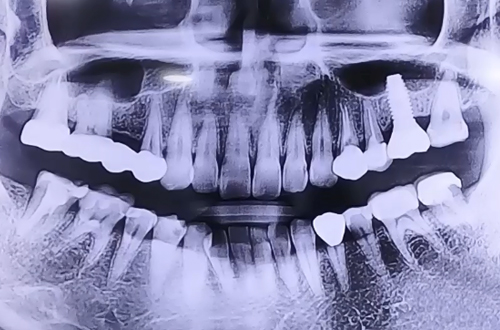

AFTER

임플란트를 바로 심었기 때문에 뼈들이 임플란트를 단단하게

둘러쌀 수 있도록 뼈이식을 통해 진행해 드린 후 임플란트

위쪽으로 이를 뺀 구멍을 메울 수 있는 뚜껑으로 덮어 놓고

4개월 후 주변 뼈들이 굳고 나면 위쪽에 큰 어금니를 제작할 계획입니다.

추후 임플란트 위쪽으로 치아머리 부분이 완성되면

다음 진료일지로 찾아뵙도록 하겠습니다^^!